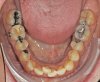

Das Quietschen fällt mir schon gar nicht mehr auf. Aber ich trage sie weiterhin fleißig. Ich kann schon sagen, dass sich der Zahn, gut eingestellt hat. Vor vier Monaten konnte ich noch die Kaufläche mit meiner Zunge beim zubeißen erfühlen. Das geht jetzt nicht mehr. Ich schaue mal, ob ich gleich noch die Fotos meiner KFO vor der Behandlung und von vier Wochen hochladen kann. Da kann man den Unterschied schon gut erkennen. Was ich als Laie halt so sagen kann. Außerdem habe ich das Gefühl, dass mein rechter vorderer Eckzahn etwas mehr Platz hat und nicht mehr so weit nach vorne steht.

Okklusion_rechts-Anfangsdiagnostik-2023_09_20-0_2[1].jpg Okklusion_Anterior-Anfangsdiagnostik-2023_09_20-0_1[2].jpg Okklusion_links-Anfangsdiagnostik-2023_09_20-0_3[1].jpg Okklusion_OK-Anfangsdiagnostik-2023_09_20-0_4[1].jpg Okklusion_UK-Anfangsdiagnostik-2023_09_20-0_5[1].jpg DSC_7646[1].JPG DSC_7649[1].JPG DSC_7651[1].JPG DSC_7652[1].JPG DSC_7655[1].JPG

Ich hoffe, ihr könnt auf diesen Bildern die Entwicklung sehen.